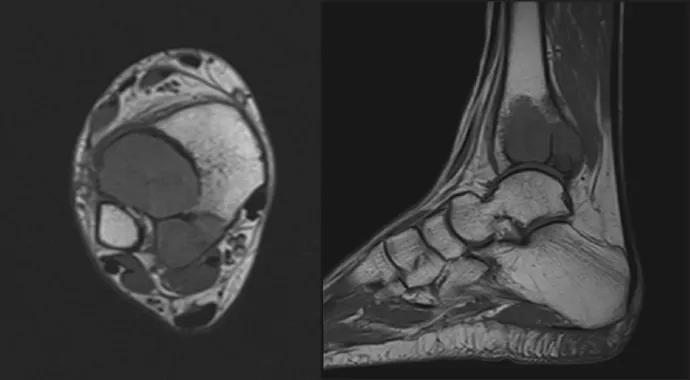

H.C. is a 35-year-old woman who had a giant cell tumor of bone removed at an outside institution. She came to Cleveland Clinic for follow-up several years after that index surgery. She had noted a subtle increase in pain, and radiographs revealed lytic lesions in the distal tibia (Figure 2), so we obtained MRIs based on concerns about the degree of bone resorption in her distal tibia. The MRIs revealed what appeared to be a recurrence of her giant cell tumor with aneurysmal bone cyst components (Figure 2).

Figure 2. Radiographs and MRIs of the case patient H.C. after presentation several years after removal of a giant cell tumor of bone. The radiographs on the top reveal two lytic lesions within the lateral aspect of the distal tibia. The MRIs on the bottom show recurrence of her giant cell tumor with aneurysmal bone cyst components

She was taken to the operating room, where a frozen section confirmed the giant cell tumor recurrence. The tumor was curetted, phenol was placed on the edges of the bone in the area of the lesion, and demineralized cortical bone powder was added. She is now back on her feet after the surgery. This case underscores the need for follow-up after giant cell tumor curettage and illustrates some common aspects of the treatment of these aggressive but benign lesions.